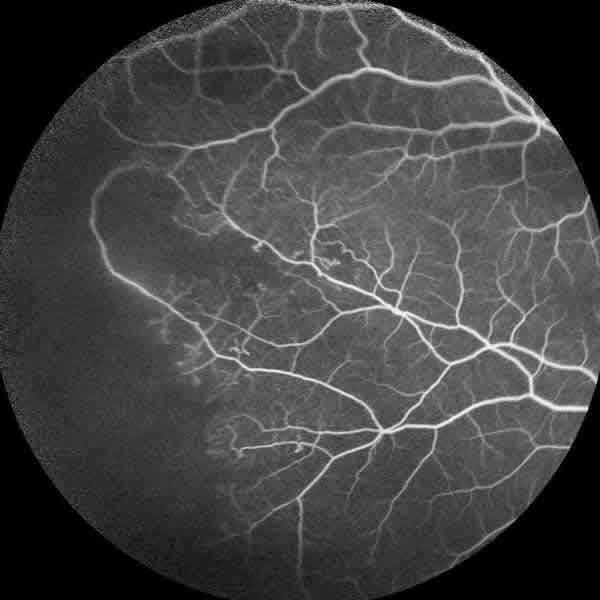

En la exploración oftalmológica la agudeza visual mejor corregida (AVMC) era de 0,6 en ambos ojos (AO). Por biomicroscopía anterior se apreciaba muy leve tortuosidad de los vasos conjuntivales, sin atrofia iridiana (fig. 1). La tonometría era de 16 mmHg. AO La funduscopía de ojo derecho (OD) mostraba oclusiones vasculares en la periferia 360 grados, con terminación muy abrupta de los mismos, telangiectasias, anastomosis arteriovenosas, zonas de no perfusión capilar, vasos hialinizados (fig. 2). El ojo izquierdo (OI) presentaba además de las lesiones descritas en el OD, neovasos muy llamativo en «abanico» en la zona temporal superior y blanco sin presión en la periferia nasal (fig. 3).

Fig. 3: Funduscopía ojo izquierdo con neovascularización "en abanico".

La angiofluoresceingrafía (fig. 4) evidenció una gran isquemia periférica y los neovasos del OI (fig. 5) pero sin isquemia macular. La tomografía de coherencia óptica tampoco demostró alteraciones foveales.

Fig. 5: Angiofluoresceingrafía de ojo izquierdo que muestra el importante complejo neovascular.